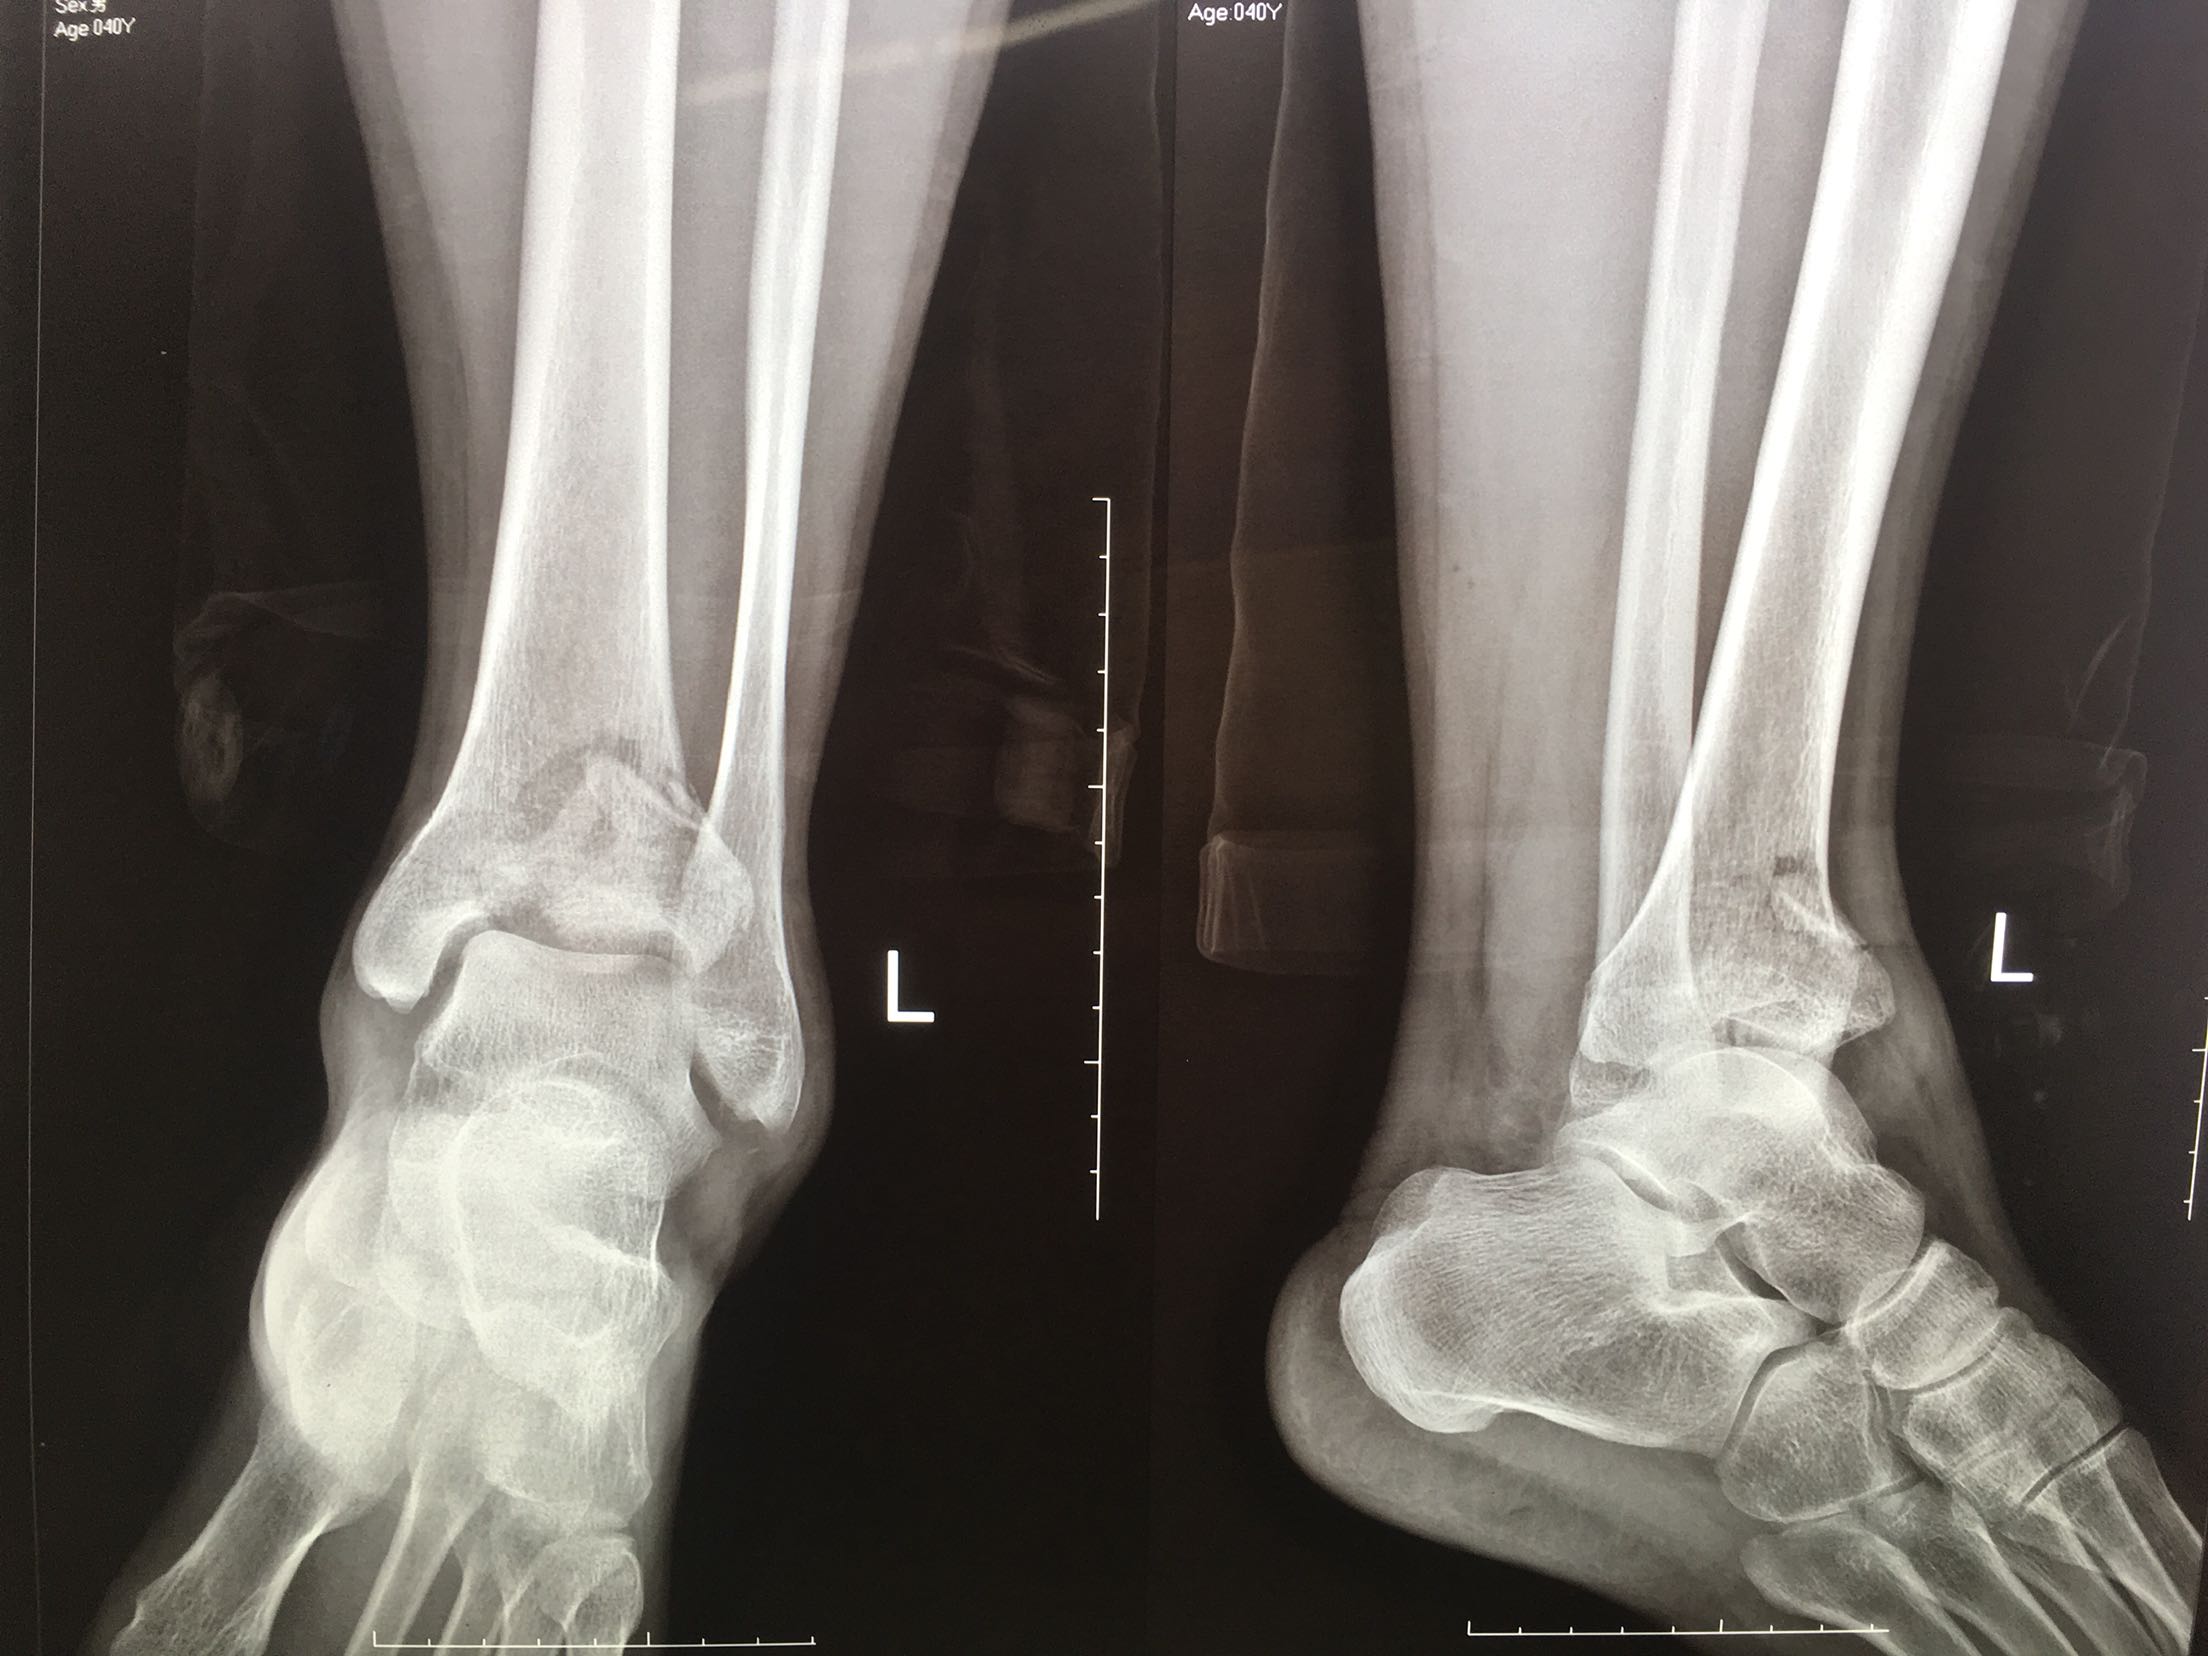

Pilon 骨折

患者,男性,41岁,坠落伤后左踝肿痛,活动受限1小时

左踝肿胀,局部皮色正常,皮温高,完整,无张力性水泡,畸形,踝关节活动受限,远端血运感觉正常。

完善检查,在腰麻下行切复内固定术,术后制动,消肿抗炎处理。